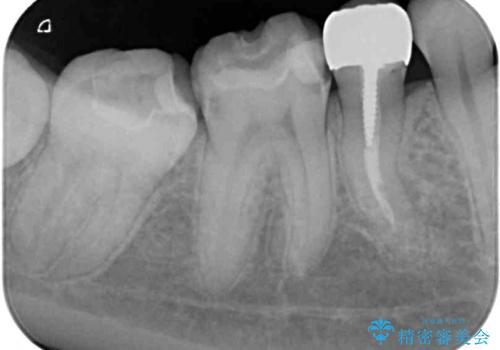

レントゲン写真から、以前治療した詰め物の下に虫歯があることがわかりました。

精度が高く、虫歯の再発リスクの低いゴールドインレーで治療を行うこととしました。